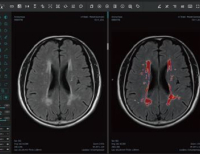

- 국립암센터, 폐암 진단 첨단 ‘로봇 기관지내시경’(Robotic-Assisted Bronchoscopy, ION) 국내 최초 도입

- 국립암센터가 폐암 진단 분야에 획기적인 전환점을 마련할 수 있는 '로봇 기관지내시경(Robotic-Assisted Bronchoscopy, ION®)'을 국내 최초로 도입한다고 밝혔...